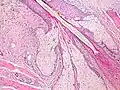

.jpg) Scalp cross section showing hair follicle with sebaceous glands.

Scalp cross section showing hair follicle with sebaceous glands. -